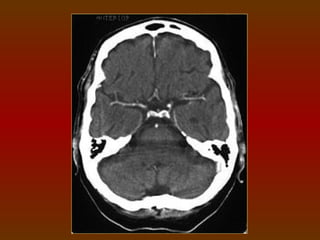

CORTE 6

a) Lobo frontal

b) Corno frontal do ventrículo lateral

c) Lobo parietal

d) Plexo coróide (calcificado)

e) Lobo occipital

f) Cápsula interna

g) Núcleo caudado